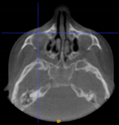

Three points determined the Acta plane: O, F right (FR), and F left (FL) (Table 2). Point O is the midpoint between the most craniodorsal point of the dorsum Sella and the most posterior dorsal point of the Basion in the midsagittal plane (Figure 1). Both points F are a result of the intersection between two lines: the line that connects the most inferior points of the lower orbital margins, right and left, and a line perpendicular to this line that runs through the most external points of the orbital margins, right and left (Figure 2). The new transverse reference plane, the Acta plane (Figure 2), is created by connecting the O-point (Figure 1) with FR and FL (Figure 2).

Figure 1.

Point O (green dot) is the midpoint between the dorsum Sella (Se) (red dot) and the Basion point (Ba) (yellow dot).